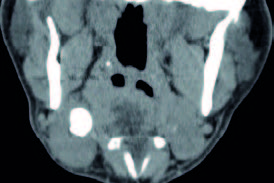

Se presentan unas imágenes de un paciente varón de 55 años, sin alergias conocidas, exfumador desde hace unos pocos años, que consulta por urgencias por inflamación brusca submandibular derecha dolorosa, tiene antecedentes de 5 episodios de submaxilitis derecha por cálculo salivar, desde hace 5 años. En la exploración de la salida sublingual del conducto de Warton se aprecia salida de saliva con supuración. Después de tratamiento antibiótico durante una semana, mejora la inflamación, saliendo saliva clara normal, quedando una hipertrofia de la glándula (figura 4).

La TAC del cuello señala una litiasis submaxilar derecha: ligero aumento del tamaño de la glándula submaxilar derecha observándose en su interior calcificación de 19 x 15 x 15 mm y otras dos pequeñas adyacentes (de 4 y 5 mm respectivamente). No se observan colecciones a nivel de la glándula submaxilar. No se observan otros hallazgos a nivel de laringe o faringe. Sin imágenes ganglionares de tamaño significativo a nivel de las cadenas ganglionares cervicales.